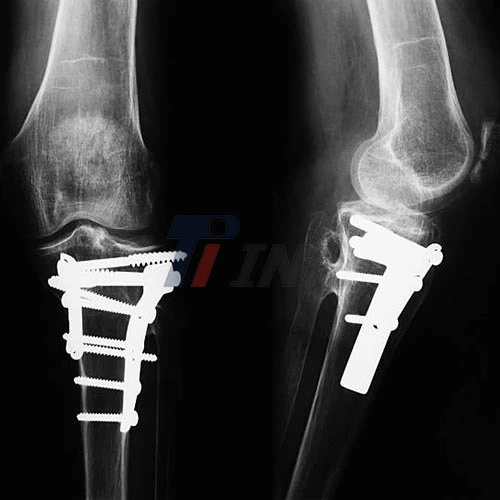

When it comes to medical implants and orthopedic surgeries, the choice of materials plays a crucial role in patient outcomes. Among the various options available, titanium plates have gained significant popularity in recent years, particularly for titanium plate in leg. But how do they stack up against other materials? Let's dive into the world of orthopedic implants and explore why titanium plates might be the superior choice for many patients.

Because titanium offers a special blend of strength, durability, and biocompatibility, it has completely changed the orthopedic surgery industry. Because of their exceptional qualities, titanium plates have become more and more common in leg surgeries.

One of the primary advantages of using a titanium plate in leg surgeries is its exceptional strength-to-weight ratio. This means that titanium plates can provide robust support for fractured bones without adding significant bulk or weight to the surgical site. For patients recovering from leg injuries, this translates to improved comfort and mobility during the healing process.

The Advantages of Titanium Plates in Leg Surgeries

Titanium's high strength-to-weight ratio makes it a perfect choice for leg plates. It can withstand the critical strengths applied on the leg during daily activities and indeed high-impact sports. This solidness guarantees that the embed can give long-term back for the mending bone without the hazard of untimely disappointment.

Titanium has a unique ability to integrate with bone tissue, a process known as osseointegration. This property is particularly beneficial for leg surgeries, as it promotes a stronger bond between the implant and the surrounding bone. The result is enhanced stability of the fracture site and potentially faster healing times.

Titanium's malleability allows for the creation of plates in various shapes and sizes, making it adaptable to different types of leg fractures and surgical requirements. This versatility enables surgeons to choose the most appropriate plate design for each patient's specific needs, potentially improving surgical outcomes.